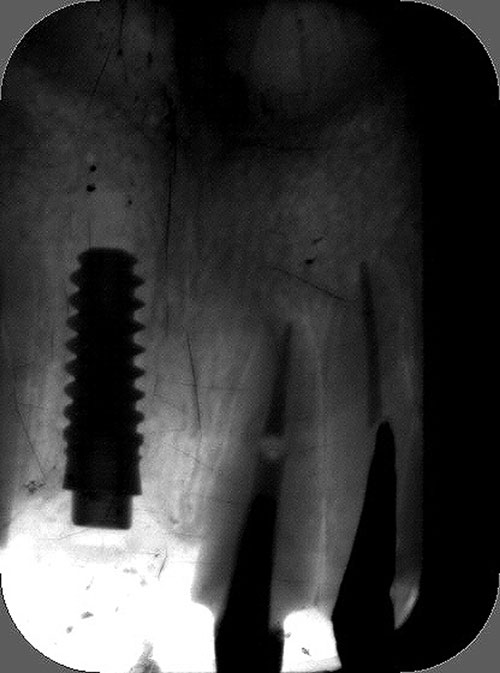

Mientras dichos movimientos ortopédicos se producen (período que supondrá otros seis meses), estudiamos los actos quirúrgicos a realizar en los cuatro implantes que pondremos. De acuerdo al estudio Desatascan realizado observamos tres situaciones diferentes: 1º-El Primer Molar Inferior Izquierdo, lo instalamos mediante Cirugía Minimamente Invasiva , con la aplicación de una Férula Quirúrgica Obtenida de los datos del scanner tratados con un programa de CMI (Cirugía Minimamente Invasiva), previa prueba en un modelo estereolitográfico, ya que la altura ósea era apenas de 9 mm. 2º- El Primer Molar Superior Derecho, se implantará mediante una ligera Elevación Atraumática (Trans alveolar) de Seno una vez logrado el espacio mesio distal necesario. 3º- El Incisivo Central Superior Derecho ausente, cuenta con un sustrato óseo prácticamente inexistente. El espesor de la tabla era de menos de 2 mm. Los caminos posibles a seguir para contar con una Rehabilitación de piezas independientes son dos: Optamos por esta segunda opción por ser menos cruenta y no necesitar de una zona dadora. Técnica esta que pondremos en práctica en dos etapas diferidas: 1º-Incisión horizontal palatinizada, incisiones peri rodetes gingivales e incisiones de descarga. Dilatación que comenzamos con dos incisiones de descarga sobre la cortical vestibular realizadas con disco. y el comienzo de la dilatación propiamente dicha mediante una hoja de bisturí, para luego seguir con un periostótomo . Recién después de alcanzada una cierta separación de la cortical vestibular de la palatina, empezamos con los dilatadores roscados. En este punto podríamos haber utilizado sin riesgos un Implante de 3,8 mm de diámetro, pero a fin de mejorar la estética del pilar emergente decidimos rellenar con material osteoconductor y osteoinductor (BiOss) y cubrir mediante membrana reabsorvible ( Bio Guide). 2º-Implantación seis meses después. Mientras se van cumpliendo los tiempos antes mencionados, y comprobamos reiteradamente la funcionalidad de la oclusión con los provisorios, tomamos impresiones definitivas y construimos primero el maxilar inferior, para definir en primer término la porción inferior de la Guía Anterior., y a nivel posterior Curvas y Microplanos. Para luego realizar los cuadrantes premolar- molar del superior: La espera de la regeneración ósea y sus tiempos pertinentes, más la espera de los tiempos de la implantación, nos obligaron a modificar las etapas del protocolo D.AT.O de manera de mantener la –D- mediante el sector superior de la GA. en provisorios, mientras fuimos resolviendo en forma definitiva los demás sectores. Ya pasados los meses necesarios para recrear un hueso adecuado en el área del Incisivo Superior Derecho, procedemos a resolver la implantación de dicha zona, observando que todo el esfuerzo dedicado al mismo había sido inútil, ya que la formación de hueso se produjo minimamente. Cuatro meses después tomamos impresiones del sector Antero Superior de la Guía Anterior, incluyendo el arrastre de un transfer . Seguimos modelando la encía con un nuevo juego de provisorios. Y se construye entonces el sector superior de la Guía Anterior. Se efectúa un control radiográfico a los 6 meses. Se ha intentado mostrar en esta Rehabilitación, que a pesar de las distintas circunstancias de cada paciente, siempre debemos tener en cuenta la necesidad de ejercer la DESOCLUSIÓN del caso como prioridad número uno, para luego perseguir la ALINEACIÓN TRIDIMENSIONAL de las arcadas y obtener así una OCLUSIÓN equilibrada. D.AT.O. ES EL PROTOCOLO QUE DEBEMOS SEGUIR EN TODA REHABILITACIÓN. BIBLIOGRAFÍA 1)William Mc Horris,B.S.,D.D.S. Oclusión. Con especial énfasis sobre :El rol funcional y parafuncional de los dientes anteriores. 2)Von Spee , Craff(Anatomista alemán, describió la curva de compensación de la articulación de molares y premolares).CURVA DE SPEE 1.89 3)Stuart,D.”Some aspects of the inervation teeth.”Procedings of Royal Society of Medicine.20:1675,19274)Muhleman,H. y Savdir,S”Tooth movility-its causes and significance”Journal of Periodontology ,36:153,Marzo ,Abril,1965. 4)Muhleman,H. Y Savdir,S”Toothmovility its causes and significance” Journal of Periodontology,36:153,marzo,abril,1965. 5-Oclusión y Diagnóstico en Rehabilitación Oral. 6-Anatomia Odontológica. 7-A contribution to the study of the movementes of the mandible. 8-Celenza F.W, Nadeskin J.F.,Oclusión.Situación actual. 9-D´Amico 10-Dawson P.E. 11-Huffman –Regenos. 12-Hobo S.-Takayama H.A. 13-Lucia V.O 14-Mc Horris. 15-Mc Horris. 16-Stuart C. 17-Vartan Veshnilian 18-Alvarez Cantoni H. AUTOR:Ratificación del Protocolo en Rehabilitación Bucal a pesar de las incidencias propias de cada caso clínico. A propósito de un caso.

Se utilizarán dos Implantes roscados de 8 mm de longitud por 3,8 mm de ancho.

El implante se encontraba perfectamente según comprobaciones radiográficas y clínicas al sondeo.